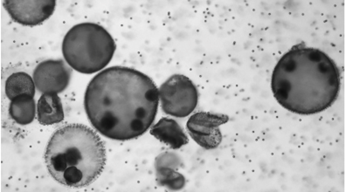

Demirci的团队使用团藻(Volvox algae)设计了他们的生物混合微型机器人,因这种藻类作为动力部分,所以机器人由此命名。它们可以通过体表数千个被称为鞭毛的毛发状突起的同步运动而移动。Demirci说:“团藻还有其他特征,比如它们天生的感知能力使它们能够向光源移动,以及可以通过光合作用产生氧气。”

团藻的扫描电镜图片(绿色伪彩)

和其他藻类一样,团藻利用叶绿素吸收光能。当暴露于红光时,它们表现出更高的光合活性和氧气产量,也正因如此,Demirci团队利用红光调节肿瘤细胞中藻类产生的氧气浓度。